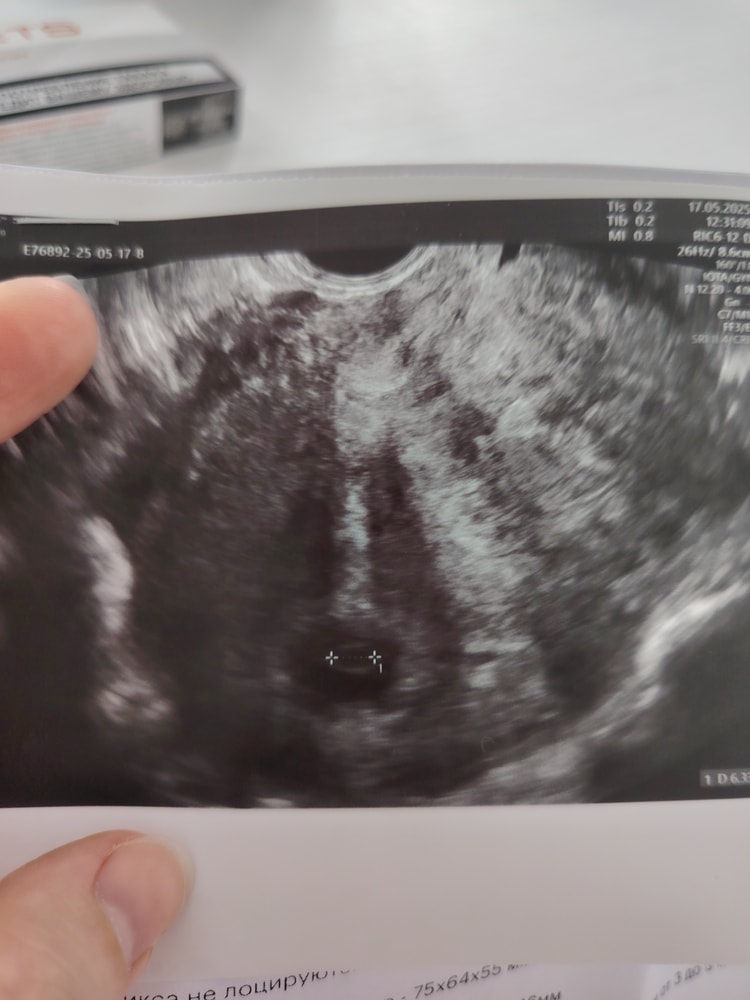

Девочки, помогайте. Узи 6 +1

Юля, сейчас у вас хорошего размера жм.не переживайте и подождите немного) я в 6,3 попала в больницу с кровянистыми выделениями и эмбрион только появился.сб не было,была только пульсация

Жм есть и это уже отлично) всё скоро появится

Юля, я конечно не хочу давать надежду. Но я вижу, сто плодное яйцо не пустое тут на узи🤷🏽‍♀️ у меня была аноэмбриония, и я четко знаю , когда оно пустое. Была просто дыра. А у вас там точка видна

Амина, спасибо большое❤️ я тоже вижу и поэтому верю🙏 в малыша.